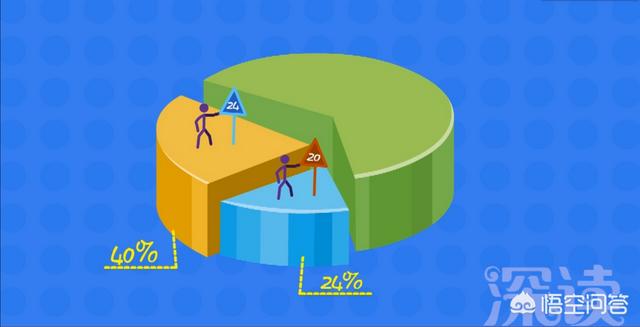

Selon les statistiques, la probabilité que ces enfants soient détectés comme diabétiques à l'âge de 20 ans est de 24 %, et de 40 % à l'âge de 24 ans.